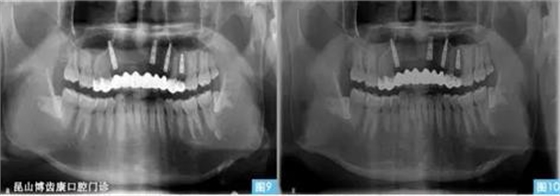

圖9圖10:(左圖9)術(shù)后3個(gè)月,(右圖10)術(shù)后6個(gè)月。